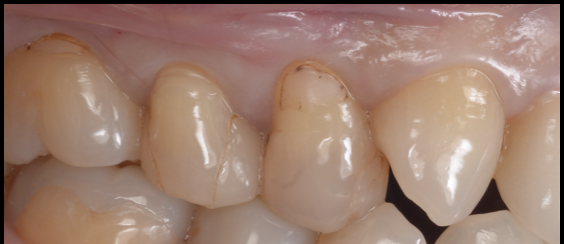

【40代 女性】

詰め物が劣化した

- 担当医

- 生野 誠

- 主訴

- 詰め物が劣化した

虫歯になってないか不安

- 期間

- 1回

- 費用

- 7万

- 治療内容

- ダイレクトボンディング

- 治療に伴うリスク

- コンポジットレジンの劣化